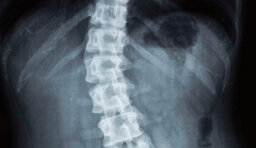

Traumi vertebrali (fratture da osteoporosi e traumatiche).

Deformità della colonna vertebrale (scoliosi, cifosi, spondiololistesi).

Patologie oncologiche della colonna (tumori primitivi, metastasi, fratture patologiche).

Patologie degenerative della colonna (ernia del disco; discopatia degenerativa, stenosi del canale vertebrale, scoliosi degenerativa dell’adulto).